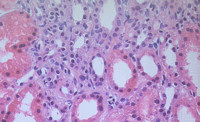

NEFROPATÍA POR OXALATO. PRESENTACIÓN DE UN CASO Y REVISIÓN BIBLIOGRÁFICA

Mejía U, E., Cuesta Rosero, D.S., Alfaro Torres, J., Vicente Arregui, S., Alastuey Aisa, M., Torrecilla Idoipe, N, Valero Torres, A.